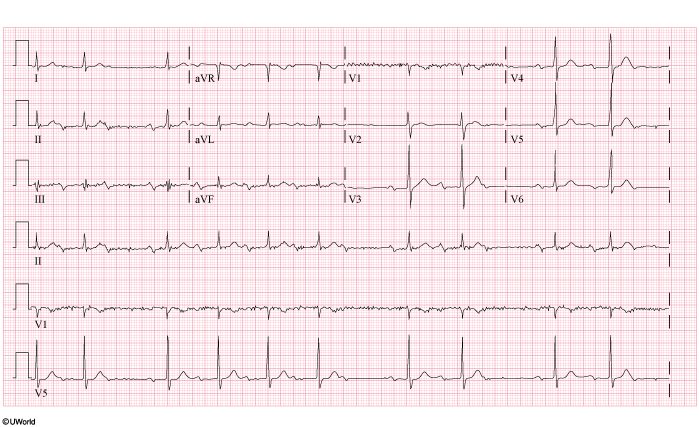

A 76-year-old man comes to the office due to increased fatigue over the past 2 months. His exercise tolerance has also decreased. The patient has had no chest pain, nausea, vomiting, dizziness, or syncope. Other medical conditions include hypertension and hyperlipidemia. Blood pressure is 124/79 mm Hg. On examination, the lungs are clear to auscultation and a short midsystolic murmur is heard over the right upper sternal border. ECG is shown in the exhibit. Which of the following is the best initial pharmacotherapy for this patient?

CorrectIncorrect